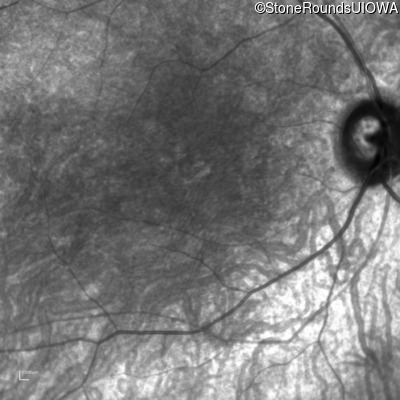

Infrared Fundus Photograph - Right - 20/200 +2

Exemplar